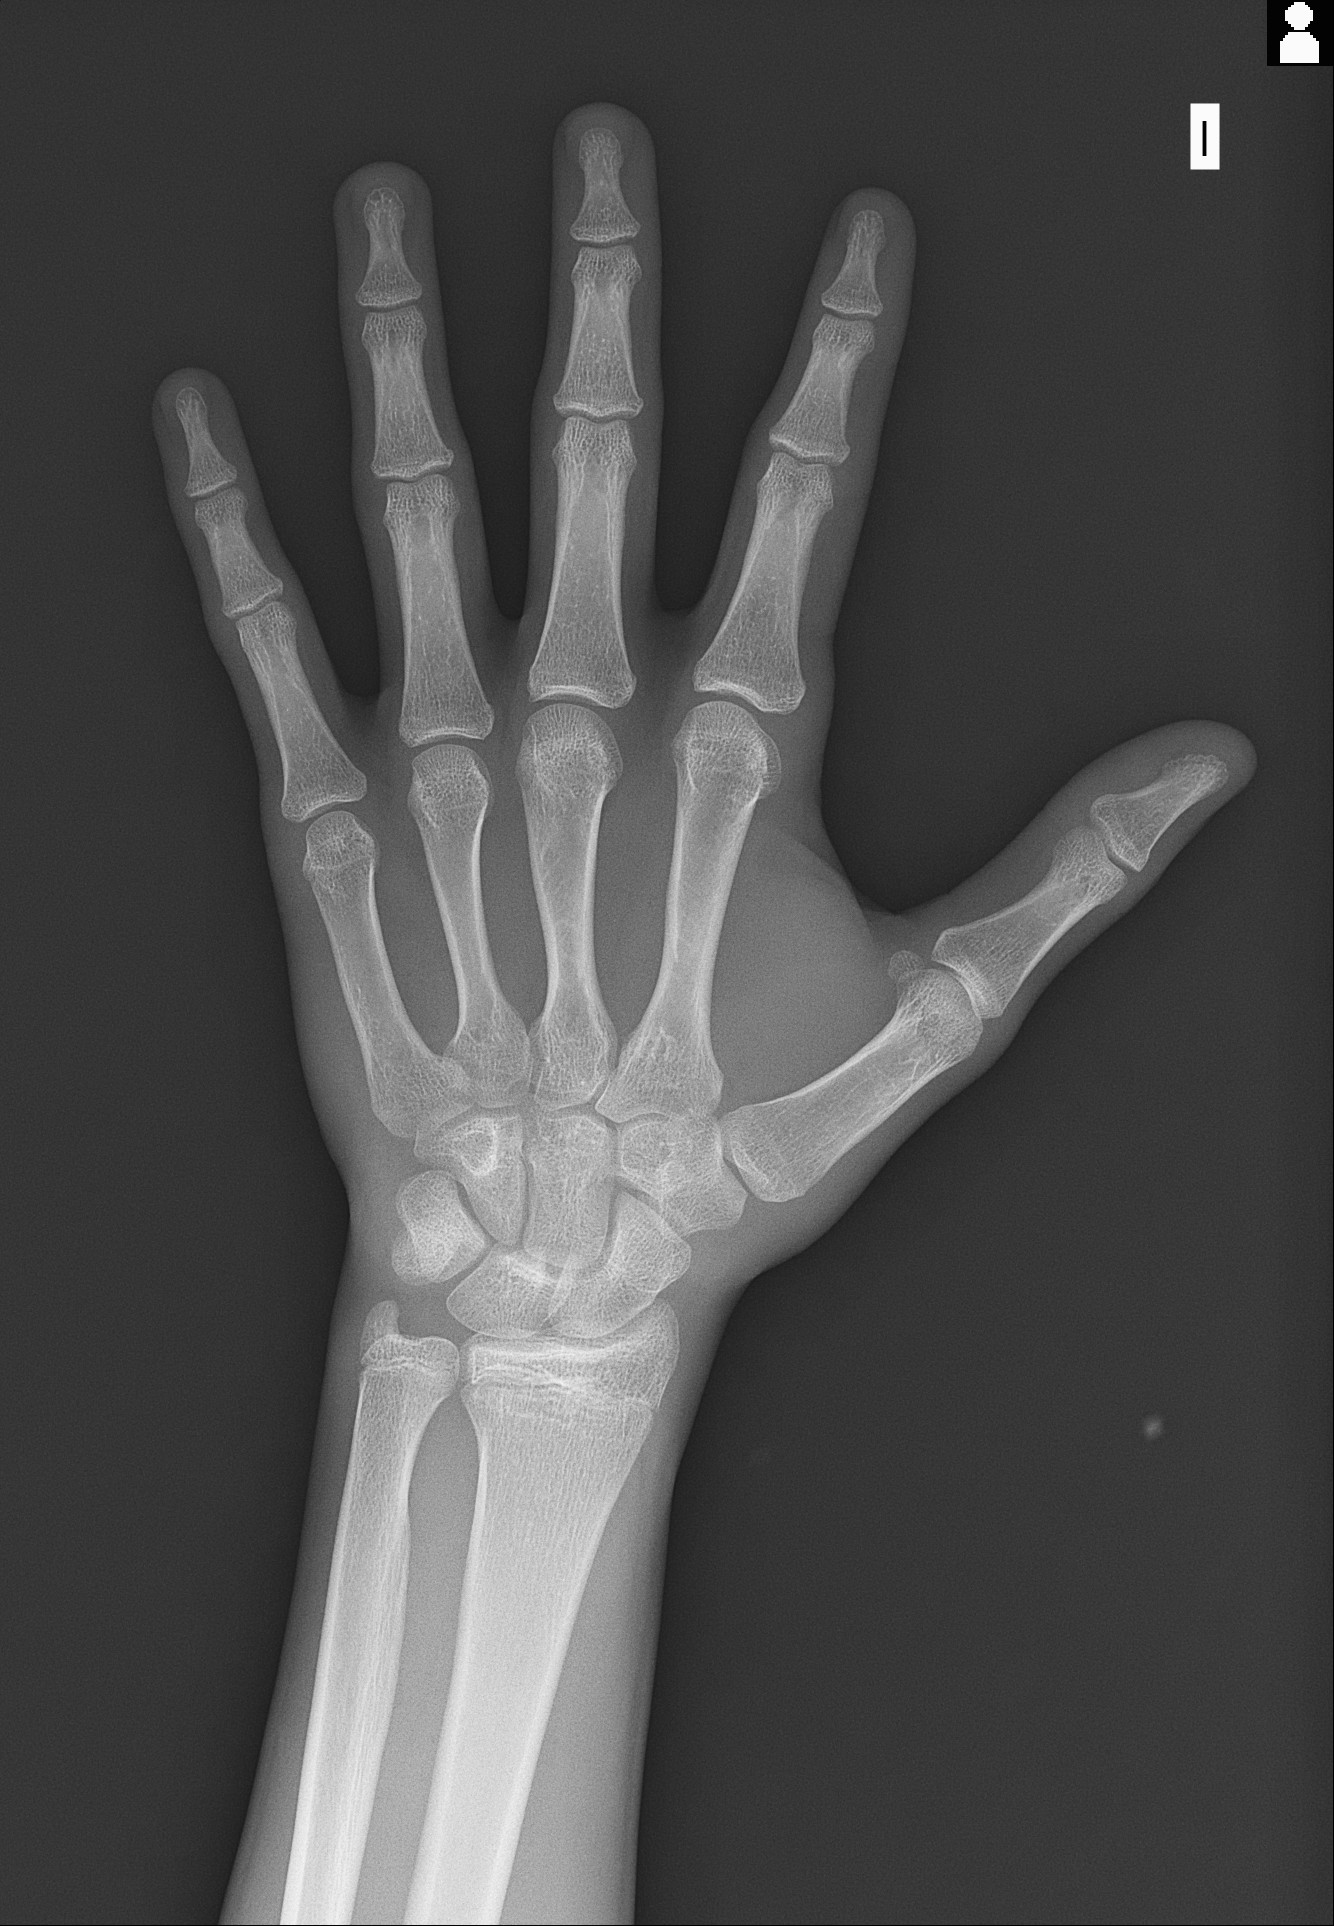

Im around 17 and my bone age, based on my calculation with using Orkas radiology thread, is 5 months older than my actual age :TriSad:.

I hopefully get the blood results of igf-1 and estradiol and other stuff soon. Im so desperate I thought I would never do it that fast but Im considering buying aromatase inhibitors (is it worth it at that late age?). Its already to late to blast hgh. Maybe ai could help. All my hand bones are already fused, my radius and ulna are the only things that arent fully closed.